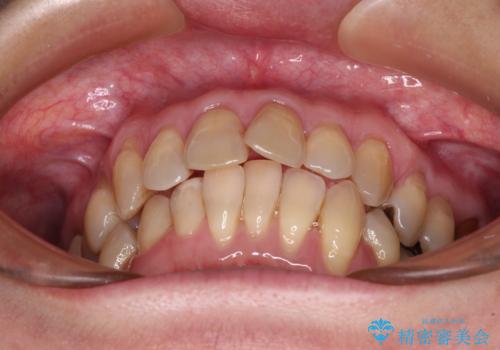

- 上下前歯のデコボコと、奥歯の銀歯を気にして来院された患者様です。

仕事柄あまり目立つ装置は付けることは避けたいとのことで、インビザラインによるマウスピース矯正を行うこととしました。

概ね歯列が整ったところで銀歯の全てをセラミッククラウンなどに置き換え、その後インビザラインを1セット使用して仕上げていくこととしました。